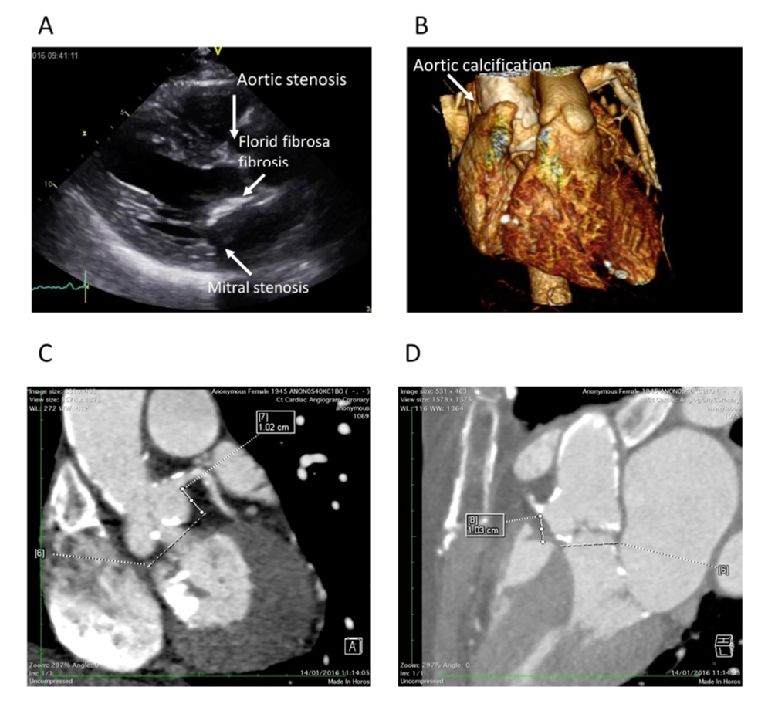

Contemporary estimates suggest that 0.5% to 2% of the population have a bicuspid aortic valve with a strong male preponderance [6]. It is associated with more rapid development of degenerative lesions (stenosis or regurgitation). Consequently, younger cohorts have a high proportion of bicuspid cases, typically between 40 and 50%. However, bicuspid disease is present in up to 20% of patients over the age of 80 [7]. It can be subtle to diagnose, particularly when the fusion of the two cusps forms a fibrous, or even calcific, raphe (Figure 1). Both echocardiography and computed tomography (CT) can be misleading [8], particularly when the valve is examined in diastole (closed), where it can be difficult to distinguish a raphe from a thickened cusp margin. Examining systolic frames and the orifice shape is strongly recommended [9].

Figure 1. A) Gated CT demonstrating accurate assessment of annular asymmetry. B) Systolic gated CT frame at the level of the aortic valve demonstrating calcification of the raphe dividing the non-coronary and right coronary cusps. This can easily be misdiagnosed as a tricuspid valve.

The anatomy poses significant potential problems for TAVI. The virtual aortic valve annulus is both large and asymmetric (Figure 1), leading to more complicated valve sizing and the potential risk of regurgitation, which is poorly tolerated in AS [10]. The valve may be less calcified, giving a higher risk of valve displacement. The presence of aortopathy in up to 70% of cases [11,12] is an additional consideration, especially where the aortic dimensions exceed 4.5 cm [13]. Emerging valve design and pre-procedural planning should address these limitations.